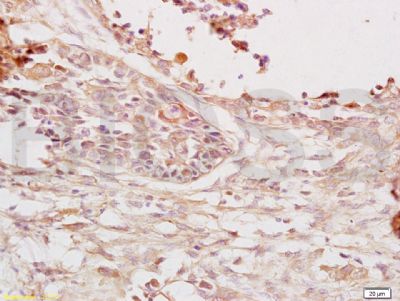

癌胚抗原免疫组化荧光抗体

产品应用WB=1:500-2000 ELISA=1:500-1000 IHC-P=1:400-800 IHC-F=1:400-800 Flow-Cyt=0.2μg/Test IF=1:100-500 (石蜡切片需做抗原修复)

CEA是一种胚胎性抗原,主要存在于胎儿消化道上皮组织,胰腺和肝癌中。CEA广泛存在各种上皮性肿瘤,尤其是胃肠道恶性肿瘤,CEA分布阳性类型与肿瘤的恶性度有关。CEA与EMA一样可作为上皮性恶性肿瘤的重要标记。